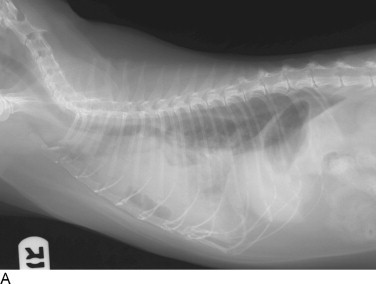

Thoracic radiographs are extremely helpful in diagnosing and quantifying pleural space disease and other intrathoracic pathology. Repeat radiographs after thoracentesis can be of diagnostic utility but were found to rarely be beneficial in providing additional diagnostic information in one human study.7 Routine radiographs after thoracentesis are considered unnecessary for stable patients in the absence of suspicion, clinical indication, or risk factors for complications (mostly pneumothorax)7,8 (Figure 30-1 ). Because the shape of the canine and feline chest is much different from that of humans, it is possible that dorsoventral radiographs in animals with pleural effusion (following thoracentesis) may still have improved diagnostic utility for evaluating the dorsal lung fields. Ultrasonographic examination is very helpful for rapid identification of pleural fluid in the emergency setting. In human medicine, indications for use of ultrasonographically guided thoracentesis include a small-volume effusion, inability to properly position the patient, failure of fluid to layer out on radiographs, and coagulopathy.9 “In veterinary medicine, ultrasound guidance is used routinely to confirm the ideal point of needle insertion for thoracentesis, mostly in patients with a small volume of effusion, fluid pockets or those at increased risk for complications.”

Figure 30-1.

Cats with pleural space disease. A, Moderate volume of malignant effusion secondary to bronchogenic adenocarcinoma. B, Pneumothorax after thoracentesis in the patient shown in A.C, Traumatic pneumothorax from high-rise syndrome. D, Spontaneous pneumothorax from diffuse pulmonary metastasis of salivary gland adenocarcinoma.